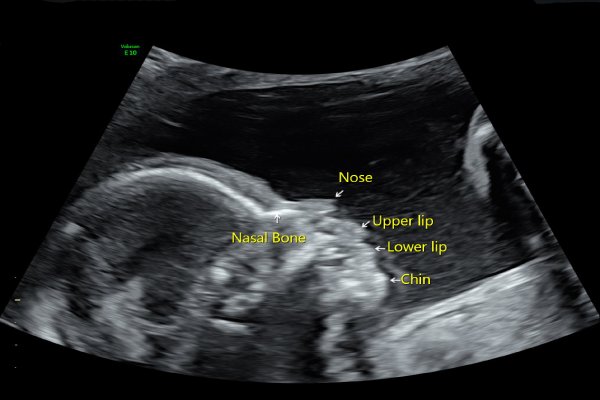

Absent Nasal Bone Treatment in Pune | Best Fetal Medicine Specialist – Dr. Deepti Mittal

Looking for reliable Absent Nasal Bone Treatment in Pune? Consult Fetal Medicine Specialist Dr. Deepti Mittal, known for her expertise in early fetal screening and accurate diagnosis. She provides advanced evaluation for absent or hypoplastic nasal bone, NT scan abnormalities, chromosomal risk assessment, and counselling on NIPT, targeted scans, and follow-up care. Trusted by expecting parents in Kharadi, Pune, she ensures timely testing, clear explanation of risks, and personalised pregnancy care.

Absent Nasal Bone Treatment in Pune | Dr. Deepti Mittal

Get expert Absent Nasal Bone Treatment in Pune with Dr. Deepti Mittal, leading fetal medicine specialist in Kharadi. Trusted for advanced fetal scans, chromosomal abnormality screening, genetic counselling, and expert evaluation for what happens if t